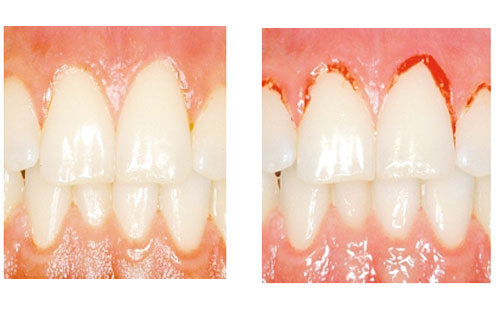

tandkött

Ett inflammerat tandkött kan se helt friskt ut. Petar man på ett inflammerat tandkött så blöder det.

Inflammerat tandkött

En inflammation i tandköttet kan vara början till parodontit. Och det är placket som bildas i munnen som är orsaken till tandköttsinflammation (gingivit). Inflammation utan parodontit är enkel att behandla. Med förbättrad munhygien läker det oftast ut på en eller ett par veckor. Dock kan inflammationen komma tillbaka snabbt om munhygienen försämras. Noggrann rengöring med tandborste, tandtråd eller liknande är det enklaste knepet för att undvika inflammerat tandkött.